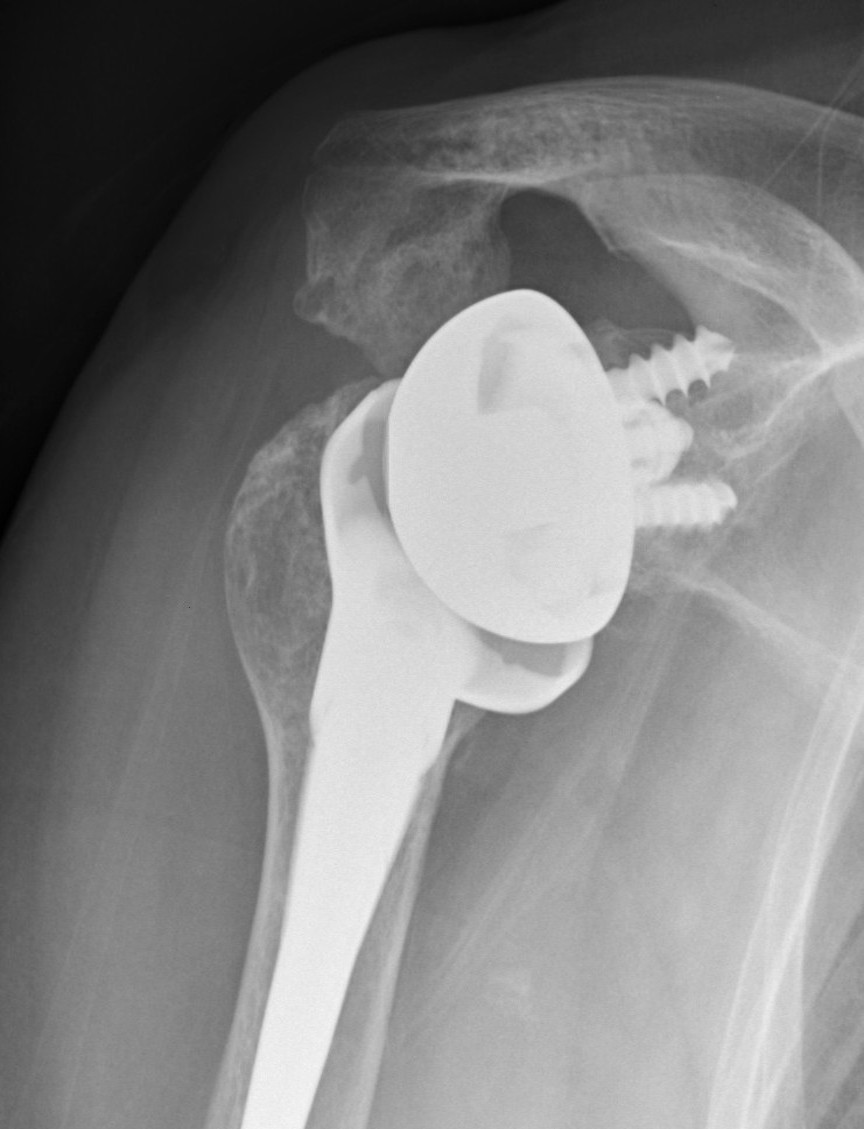

Failed Glenoid Reverse TSRReverse TSR Loose Metaglene

Loose metaglene

Lysis around humeral and glenoid component